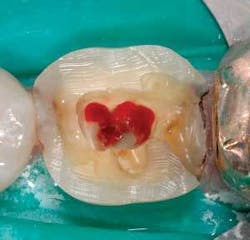

Visibility is often the limiting factor for chamber and canal identification. Rubber dam use and classic endo prep are critical. Because the general dentist is usually the professional in charge of the final restoration, it is occasionally advantageous to do the definitive restoration prep prior to doing the endo. Doing the prep first can remove tooth structure that would otherwise be in the way, and decrease the time needed to locate wayward pulp tissue (Fig. 3).

Electronic apex locators are terrific these days and, like digital X-rays, have reduced the amount of radiation exposure in many offices. These length-finding devices work best if the pulp chamber is devoid of soft tissue and blood, which is often present when the tooth is opened (see Fig. 3).